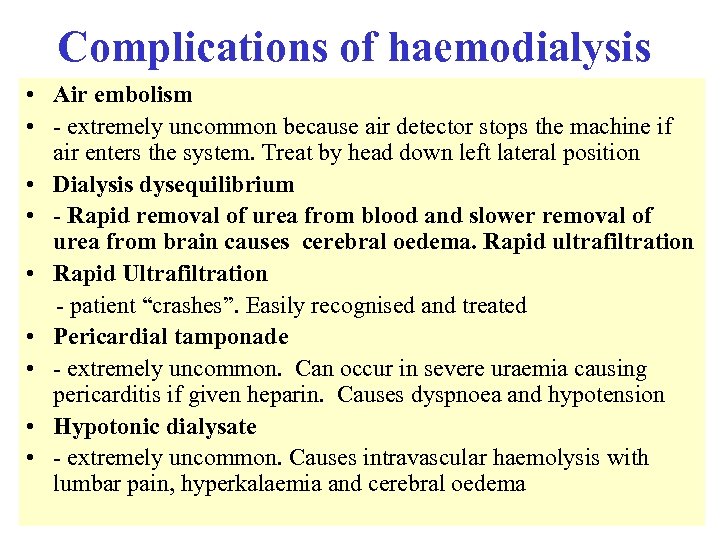

Reflux nephropathy • Treatment • - RCTs have shown equal efficacy of continuous antibiotics until puberty and ureteric reimplantation in children with reflux and UTI - reimplantation now less common than before • - prophylactic antibiotics for asymptomatic infection now no longer recommended after puberty • - only patients with serious recurrent UTI or pyonephrosis require nephrectomy before transplantation (bilateral nephrectomy not routine) • Outcome • - combination of reflux and UTI usually required to cause scarring and CRF • - but new scars rarely develop after 8 yrs of age • - progressive loss of renal function, invariably assoc with HT and proteinuria, can occur in absence of both UTI and reflux if GFR<50 ml/min • - CRF not caused by recurrent acute pyelonephritis - UTI present in a minority of adults • - accounts for ~ 20% cases ESRD requiring dialysis (not 50%)

Reflux nephropathy • Treatment • - RCTs have shown equal efficacy of continuous antibiotics until puberty and ureteric reimplantation in children with reflux and UTI - reimplantation now less common than before • - prophylactic antibiotics for asymptomatic infection now no longer recommended after puberty • - only patients with serious recurrent UTI or pyonephrosis require nephrectomy before transplantation (bilateral nephrectomy not routine) • Outcome • - combination of reflux and UTI usually required to cause scarring and CRF • - but new scars rarely develop after 8 yrs of age • - progressive loss of renal function, invariably assoc with HT and proteinuria, can occur in absence of both UTI and reflux if GFR<50 ml/min • - CRF not caused by recurrent acute pyelonephritis - UTI present in a minority of adults • - accounts for ~ 20% cases ESRD requiring dialysis (not 50%)

18 With regard to lupus nephritis: • A It may present with a rapidly progressive glomerulonephritis • B It may present with histological changes similar to diabetic nephropathy • C It should be treated with oral steroids alone when associated with a membranous histology • D It should only be treated with cytotoxic agents when serum creatinine > 120 mol/l • E Frequently complicates drug induced SLE

18 With regard to lupus nephritis: • A It may present with a rapidly progressive glomerulonephritis • B It may present with histological changes similar to diabetic nephropathy • C It should be treated with oral steroids alone when associated with a membranous histology • D It should only be treated with cytotoxic agents when serum creatinine > 120 mol/l • E Frequently complicates drug induced SLE